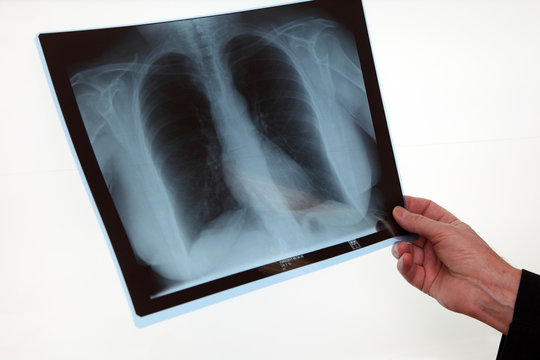

La radiographie pulmonaire Description La radiographie pulmonaire ou thoracique est un examen très couramment pratiqué Elle constitue souvent un examen de routine dans les visites d'embauche Il s'agit d'un examen radiographique qui prend tous les organes du thorax les poumons, la trachée, les bronches, la plèvre, les côtes, les clavicules.

La radiographie pulmonaire est essentiellement indiquée en cas de signes ou problèmes respiratoires toux persistante, expectorations, douleur du thorax ou de la poitrine (suite à un traumatisme par exemple). Since December 19, cases of coronavirus disease 19 (COVID19) have been emerging in Wuhan, Hubei Province, China, and the epidemic has swiftly spread to other parts of China and beyond 1 As of February 25, there were a total of 77 779 cases of diagnosed COVID19, 24 cases of suspected COVID19, 27 361 cured cases, and 2666 deaths from it in China, and there were 2464 cases of diagnosed. CHAPITRE 2 RADIOANATOMIE DU THORAX B Ghaye, C Beigelman, C Meunier, A Desir, X Boulanger, S Trogrlic and A Khalil Ce chapitre vise à rappeler l’anatomie normale du thorax et sa représentation radiologique, qu’il s’agisse de la radiographie thoracique, de la tomodensitométrie (TDM) ou de l’imagerie par résonance magnétique (IRM).

Title Microsoft Word parasitose_pulm Author omar Created Date 3/31/08 PM. Feuillets de Radiologie Vol 40 N° 5 p 349 Les pièges de la radiographie pulmonaire normale EMconsulte. La radiographie pulmonaire est recommandée en cas de troubles respiratoires, de quintes de toux persistantes accompagnées de fièvre, de douleurs thoraciques ou encore d’anomalies notées lors d’une auscultation pulmonaire classique au stéthoscope Une radio du thorax peut être demandée dans le cadre d’un bilan préopératoire.

One year after, a fibroscopy showed a necrosis of the right main bronchus mucosae and the CT showed a radioinduced aneurysm protruding into the right inferior lobular bronchus The patient eventually died a few hours later. Parenchyme pulmonaire •«Trame » = vaisseaux Ø vasculaire plus large aux bases / sommets Ø bases / sommets = 2 / 1 en position debout •Symétrie de transparence et volume des 2 hémithorax bronches visibles de façon très proximale visible 15 mm de la paroi Parenchyme pulmonaire. La radiographie pulmonaire permet aux médecins de visualiser les organes intrathoraciques comme les poumons, la trachée, les bronches, le médiastin et la plèvre (Double feuillet qui recouvre le poumon).